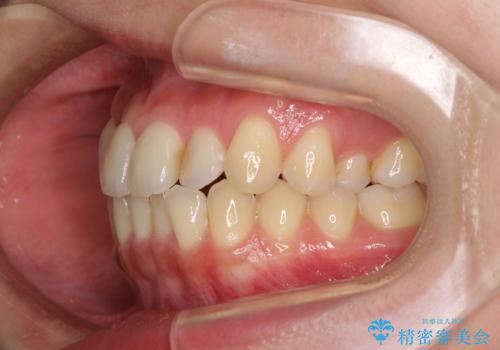

- 前歯のデコボコを気にして来院された患者様です。

上顎右側犬歯が八重歯になっており、それによって奥歯が前方に移動しているため、右側の咬み合わせの改善が必要と判断されました。

より治療を速やかに行うため、上顎右側にアンカースクリューを使用し、目標としていた1年半ほどで治療を終えることができました。